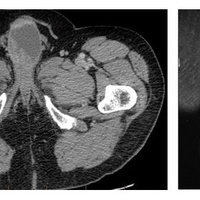

Опухоль Вильмса представляет собой высокозлокачественное новообразование, которое воздействует на паренхиму почек.